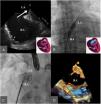

After release, the device was embolized into the left atrium and descending aorta. The right femoral artery was then canalized and the device was captured with a 30 mm gooseneck snare and externalized through the femoral artery. TEE was then performed under superficial sedation, showing an atrial septal aneurysm, with a wide PFO, and a large membrane distance generating an effective orifice of 18-20 mm. Finally, a 24 mm Amplatzer Septal Occluder (AGA Medical Corporation, Golden Valley, MN, USA) was implanted. Absence of shunt was confirmed via angiography and TTE before delivery (Figure 2). The procedure was concluded successfully and the patient was discharged the following day and prescribed treatment with 100 mg aspirin and 75 mg clopidogrel. In the following weeks there was a progressive improvement in his oxygen saturation, maintaining baseline levels over 90% and he was able to manage without domiciliary oxygen therapy.

Cribriform patent foramen ovale occluder embolization and extraction with final implant of the atrial septal defect (ASD) device. A: Transesophageal echography image where the device can be visualized with free movement at the left atrium. B: Device capture at the descending aorta. C: Device extraction through the right femoral artery. D: Final implant of the ASD device.